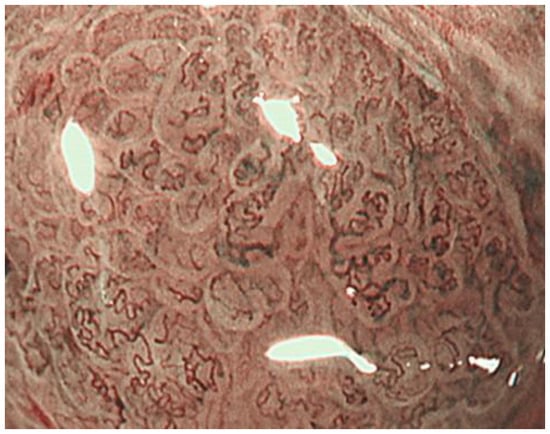

2.3. Inference of Histopathological Type of Gastric Cancer by ME-NBI